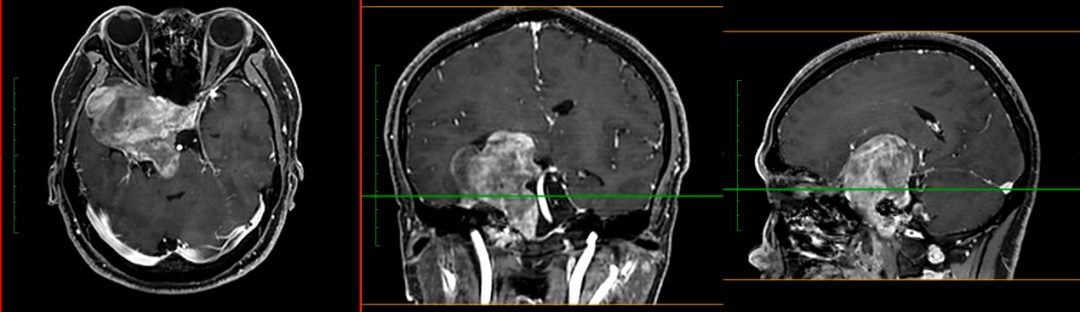

当地医院对小成头颅进行MRI检查,提示:鞍区、中颅窝及后颅窝巨大占位,脑干受压明显,且部分已侵袭突破颅底骨质,肿瘤大小约8.2*7.3*5.8cm,此外,电子视野检查发现右眼鼻侧视野、左眼颞侧视野严重缺损。

小成的这个肿瘤除了个头巨大,还很“难缠”,肿瘤和周围的血管、神经、脑组织的关系错综复杂,颅底骨质已经被肿瘤侵蚀破坏,且部分神经功能已经受到影响。

更难的是,这个肿瘤的位置也很“刁钻”,横跨了中颅窝和后颅窝两个不同的区域。如果我们把大脑看成一座两层楼的房子,那就意味着,小成的肿瘤从二楼沿梯而下,一直蔓延到了一楼。